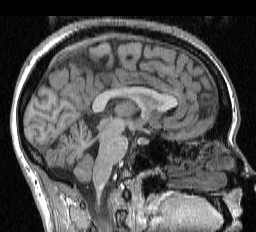

brain is isolated in a magnetic resonance imaging (MRI) volume by stripping

away all the undesired regions. For example, the cerebellum can be isolated

by stripping away the scalp, skull, cerebrospinal fluid and cerebrum in

an MRI volume. The cerebellum is located in the

lower left part of the following image. The next image illustrates various